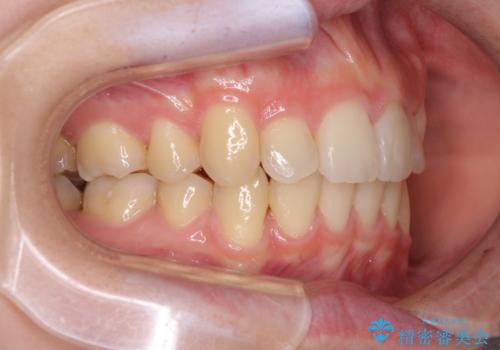

気になる八重歯を治したい ワイヤー装置での抜歯矯正

- 上下の八重歯や乱杭歯を気にして来院され患者様です。

スペースを確保するため、上下左右の第一小臼歯を抜歯し、ワイヤー装置に矯正することとしました。